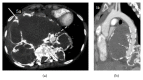

Giant cell tumor of bone (GCT) is a rare, locally aggressive neoplasm characterized by the presence of giant cells with osteoclast activity. Its biology involves the overexpression of the Receptor Activator of Nuclear Factor kB Ligand (RANKL) by osteoclast-like giant cells and tumor stromal cells, which has been shown to be an actionable target in this disease. In cases amenable to surgical resection, very few therapeutic options were available until the recent demonstration of significant activity of the anti-RANK-ligand monoclonal antibody denosumab. Here we present a case of a patient with advanced GCT arising in the spine, recurring after multiple resections and embolization. Following initiation of denosumab, which resulted in unequivocal clinical improvement, computed tomography of the chest done for reassessment purposes revealed an intratumoral pseudoaneurysm by erosion of the aorta, further corrected by endovascular approach and stent placement. Patient had an unremarkable recovery from the procedure and continued benefit from therapy with denosumab and remains on treatment 24 months after the first dose.